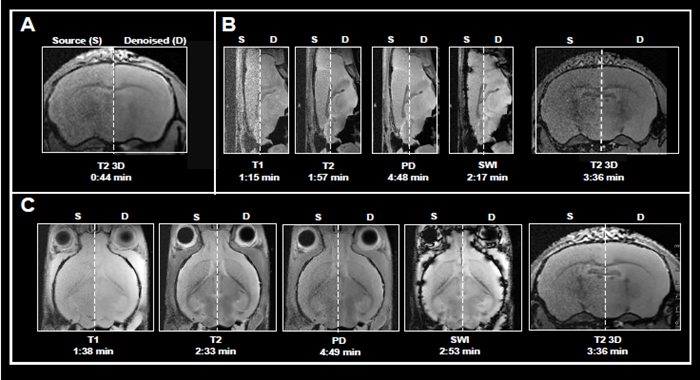

Faster imaging

MRI data acquisition is an inherently slow operation, with acquisition times increasing with higher spatial resolution, huge volumetric coverage, and/or the collection of many contrast images or quantitative data sets. Obtaining high SNR data in a reasonable acquisition time is quite desirable.

This article shows the application of Smart Noise Reduction to denoise rapid structural brain scans. Fig 4 depicts instances of ex vivo brain scans with various contrasts and orientations collected in less than five minutes. The data was collected from sensors operating at 3, 7, and 9.4 Tesla.

To accomplish the desired short acquisition time, conventional procedures produced for each system were modified to remove averaging (Fig 4A-C). This resulted in 7-15 faster acquisition times than the original protocols.

With the specified resolution, however, no averaging produced noisy images. Reconstructing the obtained data with the denoising algorithm effectively reduced noise from images and produced high-quality results.

Examples of fast brain scans

Figure 4. Examples of fast brain scans. Ex vivo data of a fixed mouse head acquired with different image contrasts, geometries and orientations. Data were acquired at A) 3 Tesla, B) 7 Tesla, and C) 9.4 Tesla. Images were reconstructed with no denoising (Source) and with a network Strong and applying 50 % pre-denoising and a denoising level of 70 % (Denoised). Image Credit: Bruker BioSpin Group